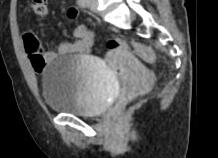

Для обследования пазух носа КТ начали применять сравнительно недавно, но врачи и пациенты успели оценить удобство процедуры. Результаты этого вида диагностики вдвое точнее, чем привычная рентгенография. КТ не вызывает дискомфорта, с которым сталкиваются пациенты на процедуре риноскопии и фиброэпифарингоскопии. Назначают обследование пазух носа в случае, когда пациент предъявляет жалобы на постоянные проблемы с дыханием. Кроме того, этот метод исследования показан при наличии постоянных или часто повторяющихся болей в лобной части головы, верхней челюсти и зубах.